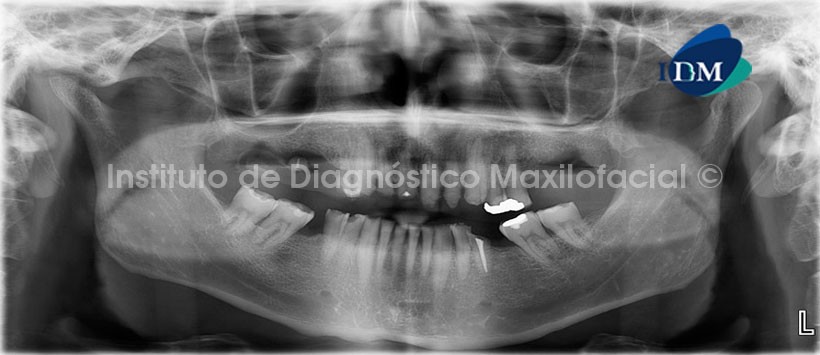

En la evaluación con tomografía volumétrica, en la reconstrucción panorámica (Fig.2) se observa la perdida de estructura dentaria mencionada, así mismo nótese la lesión apical en la pieza 1.1, la misma que en la radiografía panorámica se mostraba discretamente.